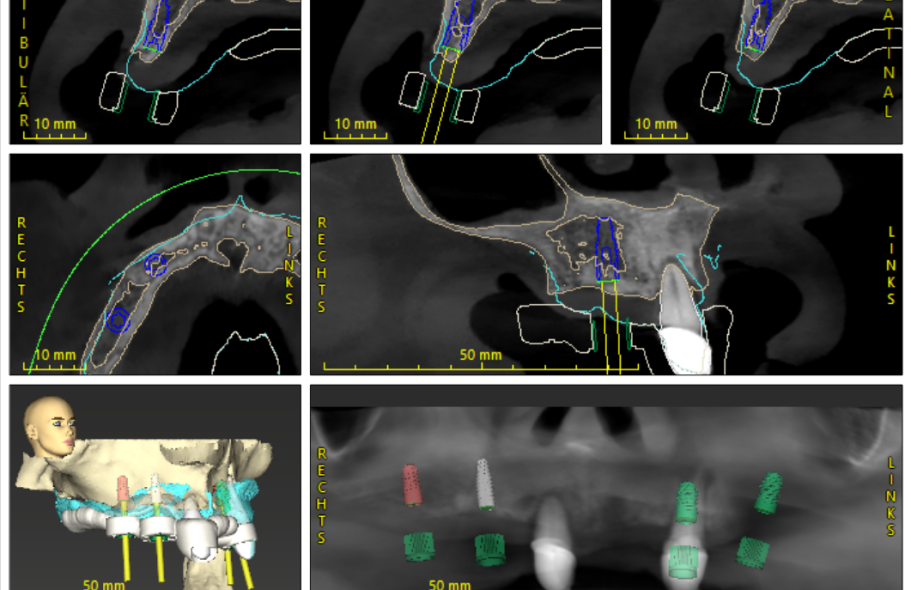

Digitale Implantatplanung

Wir setzen mit Hilfe von CoDiagnostix Implatatplanungen für Sie digital um und fertigen in höchster Präzision die navigierte Implatationshilfe für Sie an.